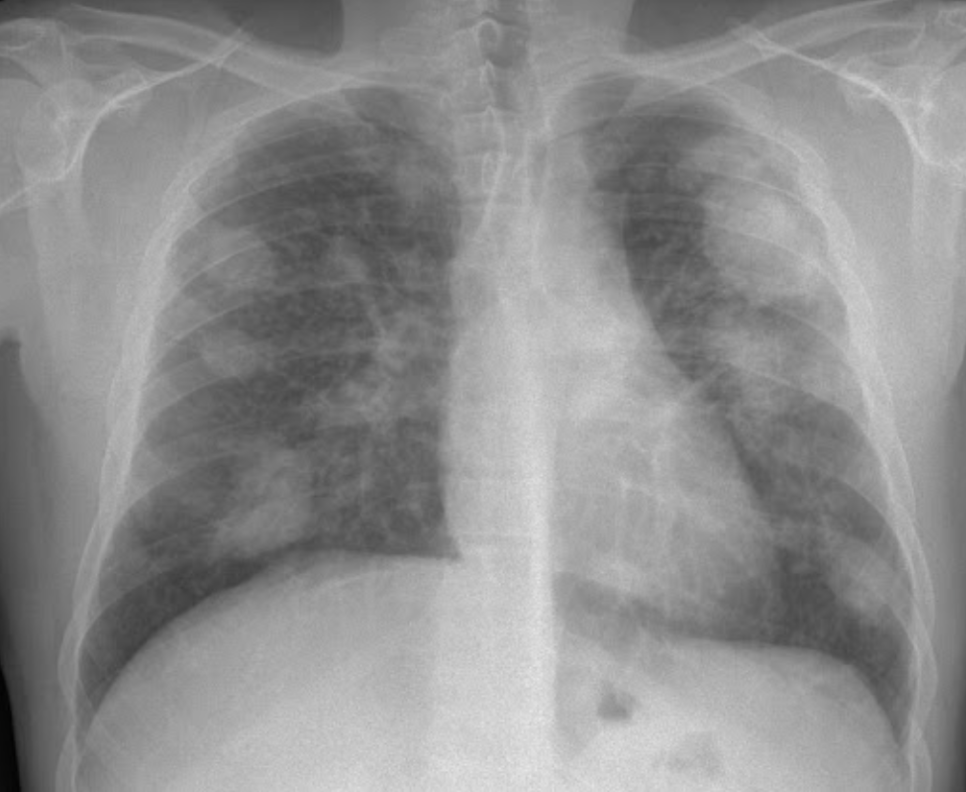

_Silicosis. Pneumoconiosis. Fibrosis. Black lung disease._ When minerals such as marble, granite, coal, and sand are extracted, transported, and refined, they release loose particulate matter — dust — that can cause irrevocable scarring in the lungs. Lesions appear as white occlusions in x-rays and CT scans, coalescing in the void of lung space. Once inhaled, the dusts of extraction can never be expelled.

The remineralization of rock strata deep within workers’ bodies should not be classified as just another “occupational hazard,” but as a form of slow violence. By perforating the earth’s finite geological crust, we are also simultaneously rupturing the lungs of miners, construction workers, tunnel drillers, sandblasters, quarry and foundry workers, stone carvers and polishers, ceramics workers, and brick workers. Some things should be left in the ground.

The lung x-ray of a worker who has silicosis with massive fibrosis. Source: https://en.wikipedia.org/wiki/File:Silicosis_complicada.jpg